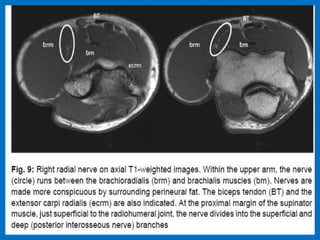

Muscles around elbow, pronator teres (Pt) brachialis

(Br) and brachioradialis (Brd) muscles.